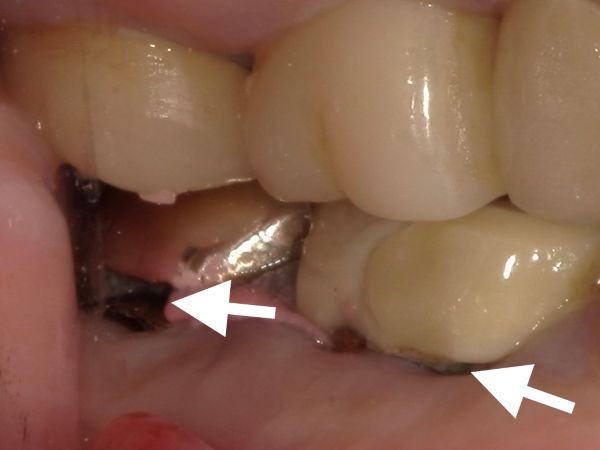

また、被せ物と歯茎の隙間に大きな虫歯があることも分かるかと思います。こちらの矢印が虫歯です。

被せ物を外して根管治療を行うこととしましたが、被せ物を実際に外して虫歯を削っていくと、かなり自分の歯の残量が少なくなってしまいました。ある程度の歯が残っていないと、被せ物をしたとしてもすぐに虫歯になってしまったり、被せ物が外れてすぐトラブルを起こしてしまいます。

患者様と相談の結果、予後不良の歯となってしまう可能性が非常に高かったため、抜歯を行い、長期的な安定が見込めるインプラント治療を行うこととしました。